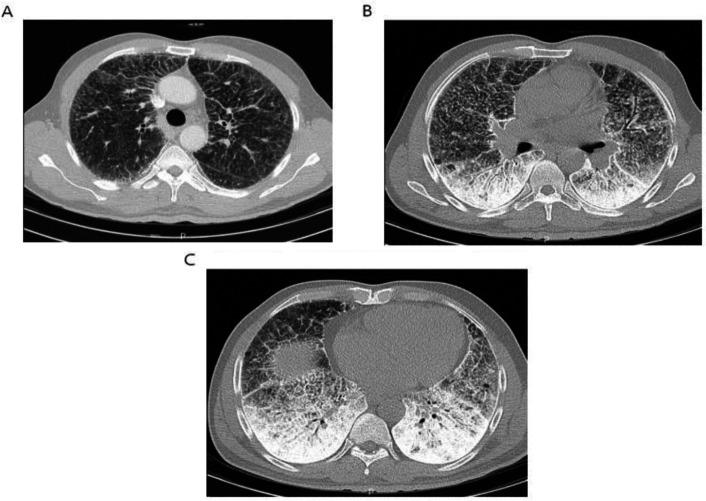

Herein, we have reported a 50-year-old male presented with recent sore throat, fever, and sweating. Radiological findings revealed bilateral micronodular pattern with diffuse ground glass attenuation in lower regions. Subsequent histologic examination of lung biopsy confirmed intra-alveolar accumulation of calculi and the diagnosis of PAM. In addition, we reviewed the literature narratively to clarify different aspects of PAM.

在此,我们报告了一名50岁男性,近期出现咽痛、发热和出汗症状。影像学检查发现双肺下叶有微结节影伴弥漫性磨玻璃影。随后的肺活检组织学检查证实肺泡内有结石堆积,确诊为PAM。此外,我们对相关文献进行了叙述性综述,以阐明PAM的不同方面。

In this paper, we presented a sporadic case of PAM which was suspected with chest x-ray and confirmed by HRCT and trans-bronchial lung biopsy. We hope that it can help clinicians to be more aware of this condition and make proper diagnosis.

本文报告了一例散发的PAM病例,通过胸部X线检查怀疑,经高分辨率CT(HRCT)和经支气管肺活检确诊。我们希望这能帮助临床医生更好地认识这种疾病并做出正确诊断。